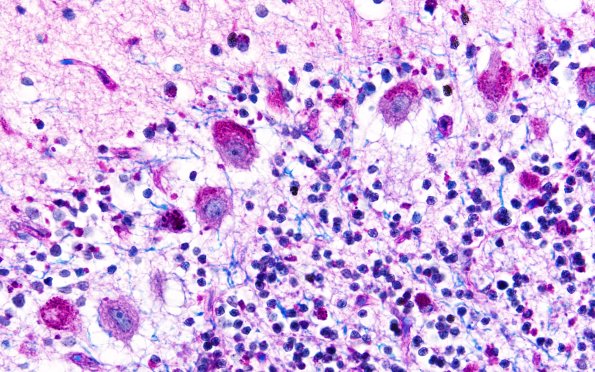

Washington University Experience | METABOLIC | Neuronal Ceroid Lipofuscinosis (NCL) | 3F2 NCL (Case 3) LFB-PAS 60X 2

A higher magnification image shows numerous Purkinje cells with PAS+ stained inclusions as well as smaller inclusions in the granule neurons. (LFB-PAS) ---- Not shown: The stored product was stained with Sudan black. ---- Comment: Hereditary adult ceroid lipofuscinosis generally is associated with the eponym Kufs disease . However this current case differs from the usual variety of Kufs disease in that the hereditary trait is dominant rather recessive and that there is prominent neuron loss in the substantia nigra. This difference has been noted earlier and this dominant variety has been called Parry disease.